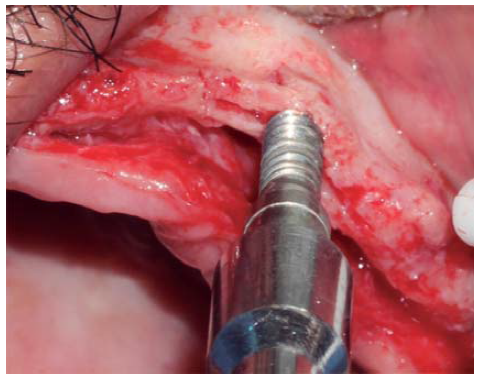

Se realizó una incisión supracrestal a espesor total, elevación del colgajo mucoperióstico exponiendo la tabla ósea hasta 4 mm de la cima de la cresta hacia vestibular y desde ese punto se dividió el colgajo a espesor parcial (Figura 3). Luego se marcaron los puntos de impacto en los sitios designados según la guía quirúrgica para la colocación de los implantes y se iniciaron las perforaciones con una fresa de 1.6 mm de diámetro para determinar el eje y profundidad deseada para los implantes. Luego se procedió a crear un surco a nivel crestal con un disco de diamante rompiendo el hueso cortical para crear el acceso a los escoplos al hueso esponjoso y con éstos se procede a separar las tablas óseas hasta llegar a una profundidad de 5 mm (Figuras 4 y 5). Seguidamente, se continuaron las perforaciones con una fresa de 2.0 mm de diámetro (Figura 6) y se realizó la expansión de la tabla vestibular creando una fractura en tallo verde con los expansores hasta alcanzar el diámetro del lecho óseo suficiente para poder utilizar la última fresa de 3.2 mm de diámetro (Figuras 7 y 8). Posteriormente, se colocaron los implantes a una velocidad de 25 rpm y a un torque de 35 Ncm (Figuras 9 y 10). Seguido de esto, se colocó un injerto óseo bovino particulado (Bonefill® Bionnovation Biomedical, Sao Paulo-Brazil), con la finalidad de preservar la integridad de las tablas óseas vestibulares (Figura 11). Todos estos procedimientos, se realizaron de la misma manera para la colocación de los seis implantes. Finalmente, se suturó con nylon monofilamento 5/0.

Figura 7 Ensanchamiento óseo utilizando expansores, creando un acceso adecuado para una fresa de mayor diámetro.